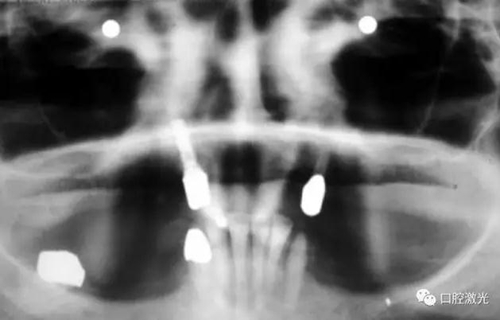

激光滅菌治療完成后,通過骨移植手術(shù)完成骨缺失的填充并縫合。一周后可以拆線。在此之后,第6周和第3個(gè)月需要進(jìn)行復(fù)診。最終的對(duì)手術(shù)區(qū)域的檢查確認(rèn)在6個(gè)月時(shí)進(jìn)行。

如今,種植體周圍炎的治療完成已經(jīng)過去了10多年,上顎義齒的狀況沒有再出現(xiàn)問題。種植體周圍組織基本健康。

治療6個(gè)月后恢復(fù)情況

治療十年以上恢復(fù)情況

如果不及時(shí)治療,種植體周圍炎會(huì)導(dǎo)致種植體失敗。在本例中,種植體的缺失將給患者的生活帶來嚴(yán)重的不便。得益于激光對(duì)種植體周圍病變組織的殺菌治療,使得發(fā)炎組織得到有效控制,同時(shí)使得周圍軟、硬組織得到了很好的保持和很快的恢復(fù)。